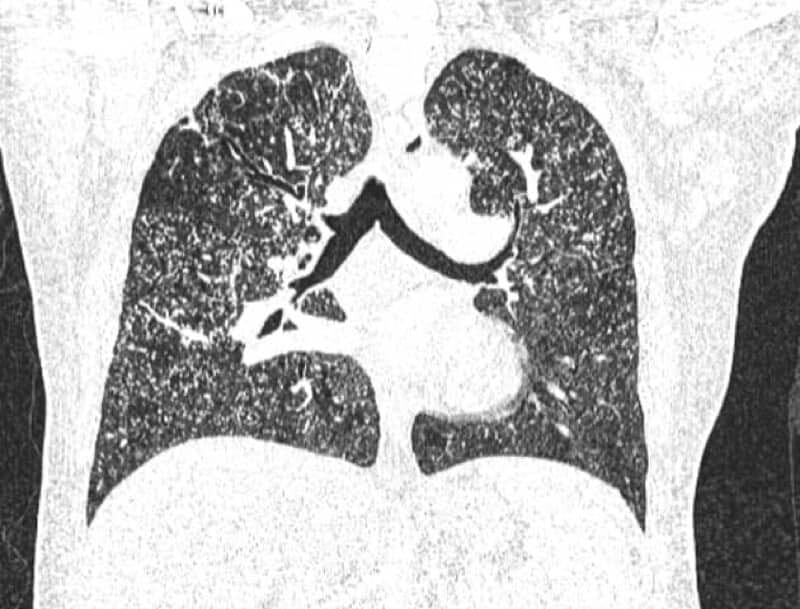

- CT: Numerous small, randomly distributed, discrete micronodules (1-2 mm) throughout bilateral lungs; typically no zonal predominance; may see associated lymphadenopathy, calcifications, or subtle consolidation; tree-in-bud nodularity may be present indicating endobronchial spread

- Signs: Miliary pattern characterized by innumerable tiny, uniform nodules resembling millet seeds distributed diffusely without zonal predilection; absence of cavitation differentiates from post-primary TB